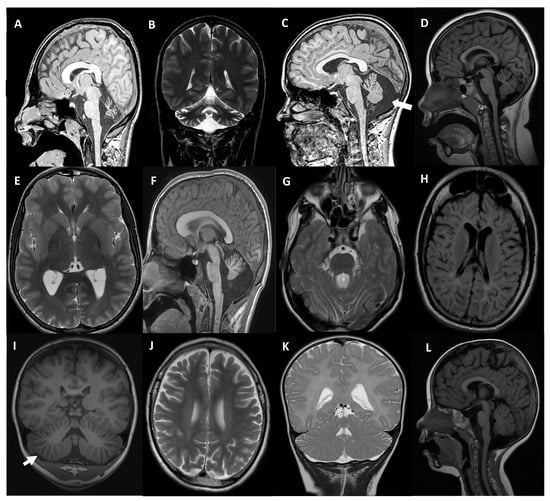

| Patient Sex | Gene | Presentation Inheritance | Disease (OMIM) | Age of Onset Age at Testing | Clinical Presentation | Brain MRI | Cognitive Involvement | Other Neurological Phenotypic Characteristics |

|---|---|---|---|---|---|---|---|---|

| MD-359 female | SETX | Sporadic AR | SCA with axonal neuropathy (606002) | 6 yo 8 yo | Mild truncal ataxia. Bilateral sensorineural deafness. | CA | Average IQ | Learning difficulties |

| MD-353 male | CACNA1G | de novo AD | SCA42 (616795) SCA42 early-onset, severe, with neurodevelopmental deficits (618087) | At birth 17 yo | Congenital arthrogryposis. Ataxia. Gait instability. Dysmetria. | Moderate CA | Moderate Attention deficit | Moderate-severe speech delay. Dystonic head movements. Nystagmus |

| MD-309 male | CACNA1A | de novo AD | Episodic Ataxia type 2 (108500) SCA6 (183086) Developmental and epileptic encephalopathy 42 (617106) Familial hemiplegic migraine type 1 (141500) | 18 mo 12 yo | Gait instability. Basal nystagmus. Dysmetria. Episodes of increased instability that last hours. | Mild vermian atrophy | Mild IQ | Arreflexia |

| MD-556 female | CACNA1A | de novo AD | 6 mo 12 yo | Paroxysmal, episodic, vertigo-like disorder triggered by emotions or fever. Gait instability. | Mild vermian atrophy | Borderline IQ | Strabismus. Mild gait ataxia. EEG abnormalities | |

| MD-471 male | CLN6 | Familial AR | Neuronal Ceroid Lipofuscinosis Type 6A (601780) Type 6B (204300) | 3 yo 5 yo | Dysarthria. Gait instability. ADHD symptoms. | CA White matter T2/FLAIR hyperintensity | Progressive decline | Drop attacks. Visual deficit and gait loss from 6-yo. |

| MD-472 † female | 3 yo 3 yo | Mild stuttering. | Enlarged cerebellar folia, white matter T2/FLAIR hyperintensity | Mild attention deficit | Gait instability, loss of speech and cognitive decline from 4-yo. | |||

| MD-548 male | MAST1 | de novo AD | Mega-corpus-callosum syndrome with cerebellar hypoplasia and cortical malformations (618273) | At birth 13 yo | Ataxia. Lack of speech. | Megacorpus callosum with CA | Severe ID | Absence of language. Mild facial dysmorphic features. Tented upper lip, pointed palate |

| MD-392 male | CPLANE1 | Sporadic AR | Joubert syndrome 17 (614615) | 18 mo 17 yo | Motor delay (independent walk 2 yo). | Molar tooth sign. Cerebellar hypoplasia | Borderline IQ | Ataxia. Oculomotor apraxia. ADHD. |

| MD-297 female | TBCD | Sporadic AR | Early-onset progressive encephalopathy with brain atrophy and thin corpus callosum (PEBAT) (617193) | 15 mo 18 yo | Seizures. Motor impairment. | Progressive CA | Severe ID | Encephalopathy Spastic-dystonic tetraparesis |

| MD-610 male | PI4KA | Sporadic AR | Neurodevelopmental disorder with spasticity, hypomyelinating leukodystrophy, and brain abnormalities (NEDSPLB) (616531) | 20 mo 36 mo | Acute ataxia. | Diffuse hypomyelination Enlarged cerebellar folia | No | Progressive lower limbs spasticity |

| MD-436 female | CLK2 | de novo AD | - | 17 mo 5 yo | Motor delay. Gait instability. Oculomotor apraxia. | Subtle enlargement of vermian folia | Borderline IQ | Global improvement over age. Language delay |